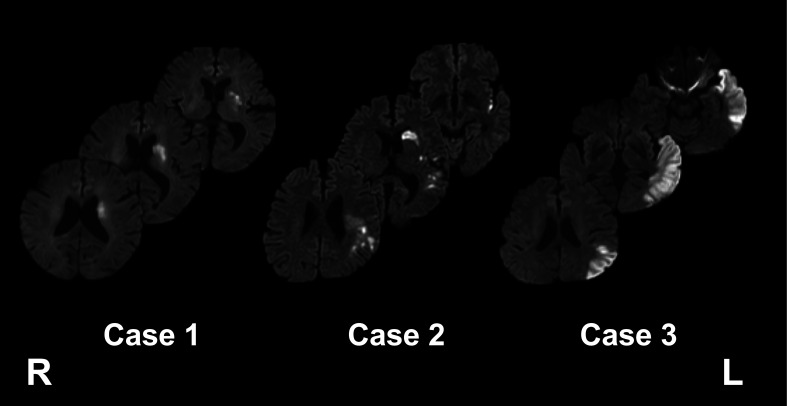

Cases: Diffusion-tensor images were acquired from three patients on days 10-14. Brain images were processed by XTRACT, which automatically extracts neural tracts using standardized protocols. Fractional anisotropy (FA) values were then bilaterally evaluated in the following neural tracts associated with aphasia: arcuate fasciculus, inferior fronto-occipital fasciculus, middle longitudinal fasciculus, inferior longitudinal fasciculus, and uncinate fasciculus. Case 1 had word-finding difficulty on admission. FA values in the lesioned left hemisphere were not decreased in all tracts and this patient fully recovered during acute care. Case 2 had reduced spontaneous speech and a low FA value in the left arcuate fasciculus. Rehabilitative treatment was scheduled to improve the verbal output of sentences and word recall. Case 3 could not complete the conventional aphasia test battery because of attention disturbance. He had low FA values in all tracts in the left hemisphere. Rehabilitative treatment was designed to focus on both speaking and auditory comprehension.